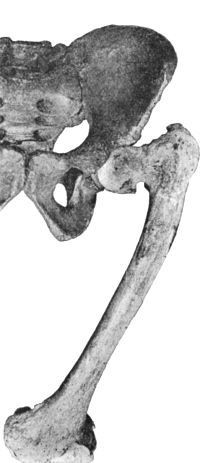

29 12.Os Innominatum showing new Socket formed after Old-standing Dislocation

250 130.Congenital Dislocation of Left Hip in a Girl

251 131.Contracture Deformities of Upper and Lower Limbs resulting from Spastic Cerebral Palsy in Infancy